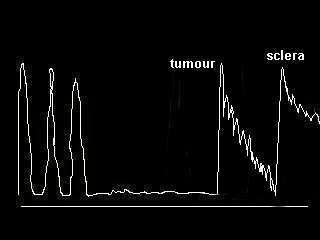

c. Tumours

-

The most likely tumour is choroidal melanoma. Occasionally

you may be given retinoblastoma, the age is a clue.

-

In choroidal melanoma, look for excavation, associated choroidal

or retinal detachment and scleral invasion.